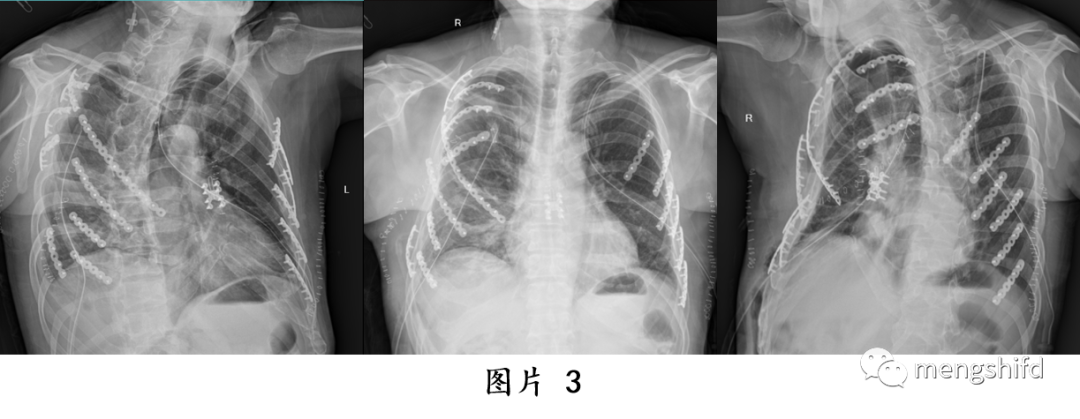

多发肋骨骨折和胸骨骨折合并连枷胸的手术治疗方法